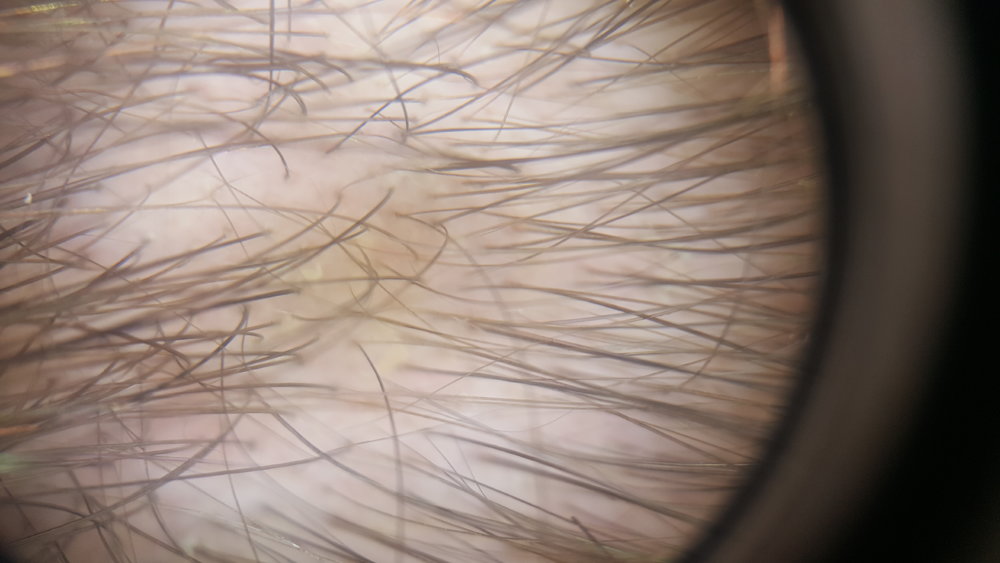

So I was today at dermatolog for a recheck for hair. She said to me that I don't have to worry much since I am having new hair growing(she meant for this thin golden hair).

Can anyone of you spot that too or maybe she was just trying to make me feel better (since I'm suffering the hair thinning)